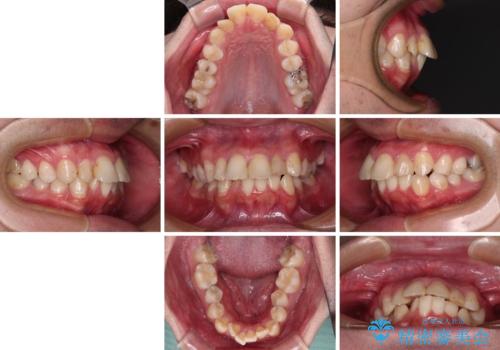

- 口元の突出感と奥歯の咬み合わせの悪さを気にして来院された患者様です。

口元はやや突出感があったため、上下左右の第一小臼歯4本を抜歯してワイヤー矯正にて抜歯矯正を行うこととしました。

また、左右ともに最後臼歯が交叉咬合になっており、外側に飛び出している上顎の最後臼歯を補助装置を利用して、積極的に内側に引き込むようにしました。